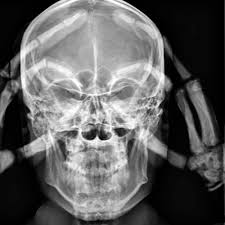

rayos X contienen muchos riesgos para el  humano y las células, pero al mismo tiempo proporcionan beneficios en el sentido de que ayudan a los médicos a comprender lo que está mal con el cuerpo de un paciente, por dentro y por fuera. Mientras que son obviamente necesarios para el campo de la medicina, por desgracia, los rayos X son perjudiciales para el paciente que los recibe, el técnico de rayos que administra el procedimiento y cualquiera en la zona donde se estén utilizando los rayos X. Es importante conocer esto

Los efectos nocivos de los rayos X son muchos. Los efectos biológicos de radiación son muy destructivos para cualquier tipo de tejido vivo y en una persona puede causar la mutación de ADN. El daño del ADN puede provocar el suicidio celular y la división celular aleatoria, la latencia de la célula y, posiblemente, incluso formar un tumor canceroso (irónico ya que la radiación se utiliza para deshacerse de las células cancerosas). Los rayos X pueden ser muy perjudiciales para una mujer que está embarazada y pueden causar defectos en el bebé y afectar el proceso del parto. El sistema de la sangre puede ser afectados por la radiación. Si las células rojas de la sangre son afectadas, puedes sufrir de anemia y si las células blancas de la sangre se ven afectadas, pueden activar el sistema inmunológico y el cuerpo y te harás susceptible a incluso la más leve de las enfermedades e infecciones. Los genitales y el sistema reproductivo pueden ser afectados con el cambio celular y puede hacer que se vuelvan estériles. La médula ósea es también muy probable que se vea afectada por los rayos X, que es el tejido dentro de los huesos. El daño de la médula ósea afecta a los folículos de la piel y el pelo , lo que resultará en la pérdida del cabello, erupciones y enrojecimiento del tejido de la piel.

Imagen relacionada